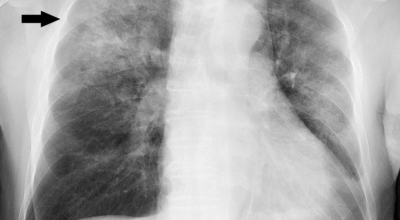

폐렴은 생각보다 무서운 병이지요. 펴렴 초기 증상 폐렴을 진단받고 현대의약으로 치료가 가능하나 폐렴 초기 증상을 방치한다면 심각한 질병으로 심각한 상황으로 갈 수 있으므로 폐렴 초기증상이 있으면 병원에서 제대로 된 검사를 받는 것이 중요해요. 오늘은 폐렴 증상에 관하여 알려드려요.

폐렴은 폐의 감염으로 인해 발생해요. 대부분의 감염은 박테리아나 바이러스에 의해 발생하지만 종종 원인을 찾을 수 없어요. 감기나 독감에 의해 유발될 수 있고, 이로 인해 세균이 폐에 접근할 수 있어요. 세균성 폐렴은 폐렴구균 박테리아에 의해 발생할 수 있어요. 이것은 가장 심각하고 잠재적으로 생명을 위협하는 유형의 폐렴 중 한가지이예요.